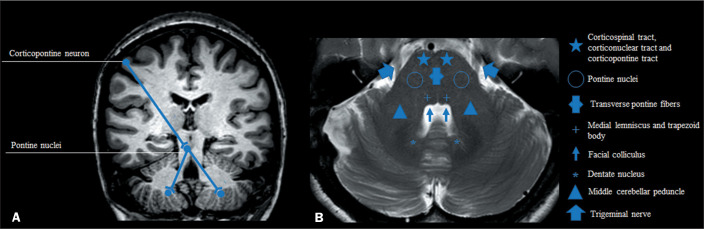

小脑中脚(MCP)是小脑最大的传入系统,由皮质-桥-小脑束纤维组成。具体来说,一些相关疾病在T2加权/液体衰减反转恢复(T2/FLAIR)磁共振成像序列上可表现为MCP高强度,包括多发性硬化症;急性播散性脑脊髓炎;视神经脊髓炎;进行性多灶性白质脑病;肝性脑病;渗透性脱髓鞘综合征;多系统萎缩;脆性x相关震颤/共济失调综合征;伴有皮质下囊肿的巨脑性白质脑病;脊髓小脑的共济失调;半桥脑梗死伴轴突变性;组蛋白H3K27M突变的弥漫性中线胶质瘤。这篇图片综述的目的是讨论T2/FLAIR序列上以MCP高强度表现的疾病的鉴别诊断相关的影像学表现。这些知识对执业放射科医生来说是至关重要的。

The middle cerebellar peduncle (MCP) is the largest afferent system of the cerebellum and consists of fibres from the cortico-ponto-cerebellar tract. Specifically, several relevant diseases can present with hyperintensity in the MCP on T2-weighted/fluid-attenuated inversion recovery (T2/FLAIR) magnetic resonance imaging sequences, including multiple sclerosis; acute disseminated encephalomyelitis; neuromyelitis optica spectrum disorder; progressive multifocal leucoencephalopathy; hepatic encephalopathy; osmotic demyelination syndrome; multiple system atrophy; fragile X-associated tremor/ataxia syndrome; megalencephalic leucoencephalopathy with subcortical cysts; spinocerebellar ataxias; hemi-pontine infarct with trans-axonal degeneration; and diffuse midline glioma with the histone H3K27M mutation. The aim of this pictorial review is to discuss the imaging findings that are relevant for the differential diagnosis of diseases presenting with MCP hyperintensity on T2/FLAIR sequences. Such knowledge is of utmost importance for the practicing radiologist.